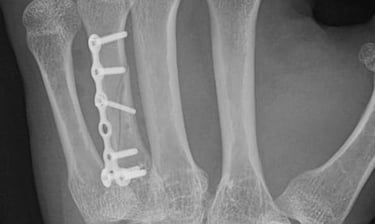

Artroscopia de muñeca

Cirugía mínimamente invasiva para la patología más compleja de la muñeca